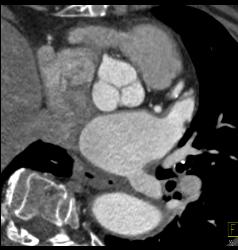

Supravalvular Stenosis and Prior Myocardial Infarction